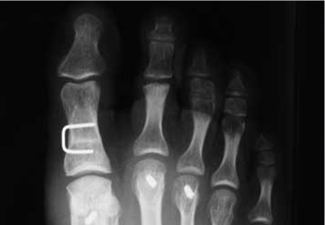

Hallux Valgus clásico: notese la deformidad que produce el tendón aductor.

Desplazamiento clásico obtenido con la oesteotomía en chevron.